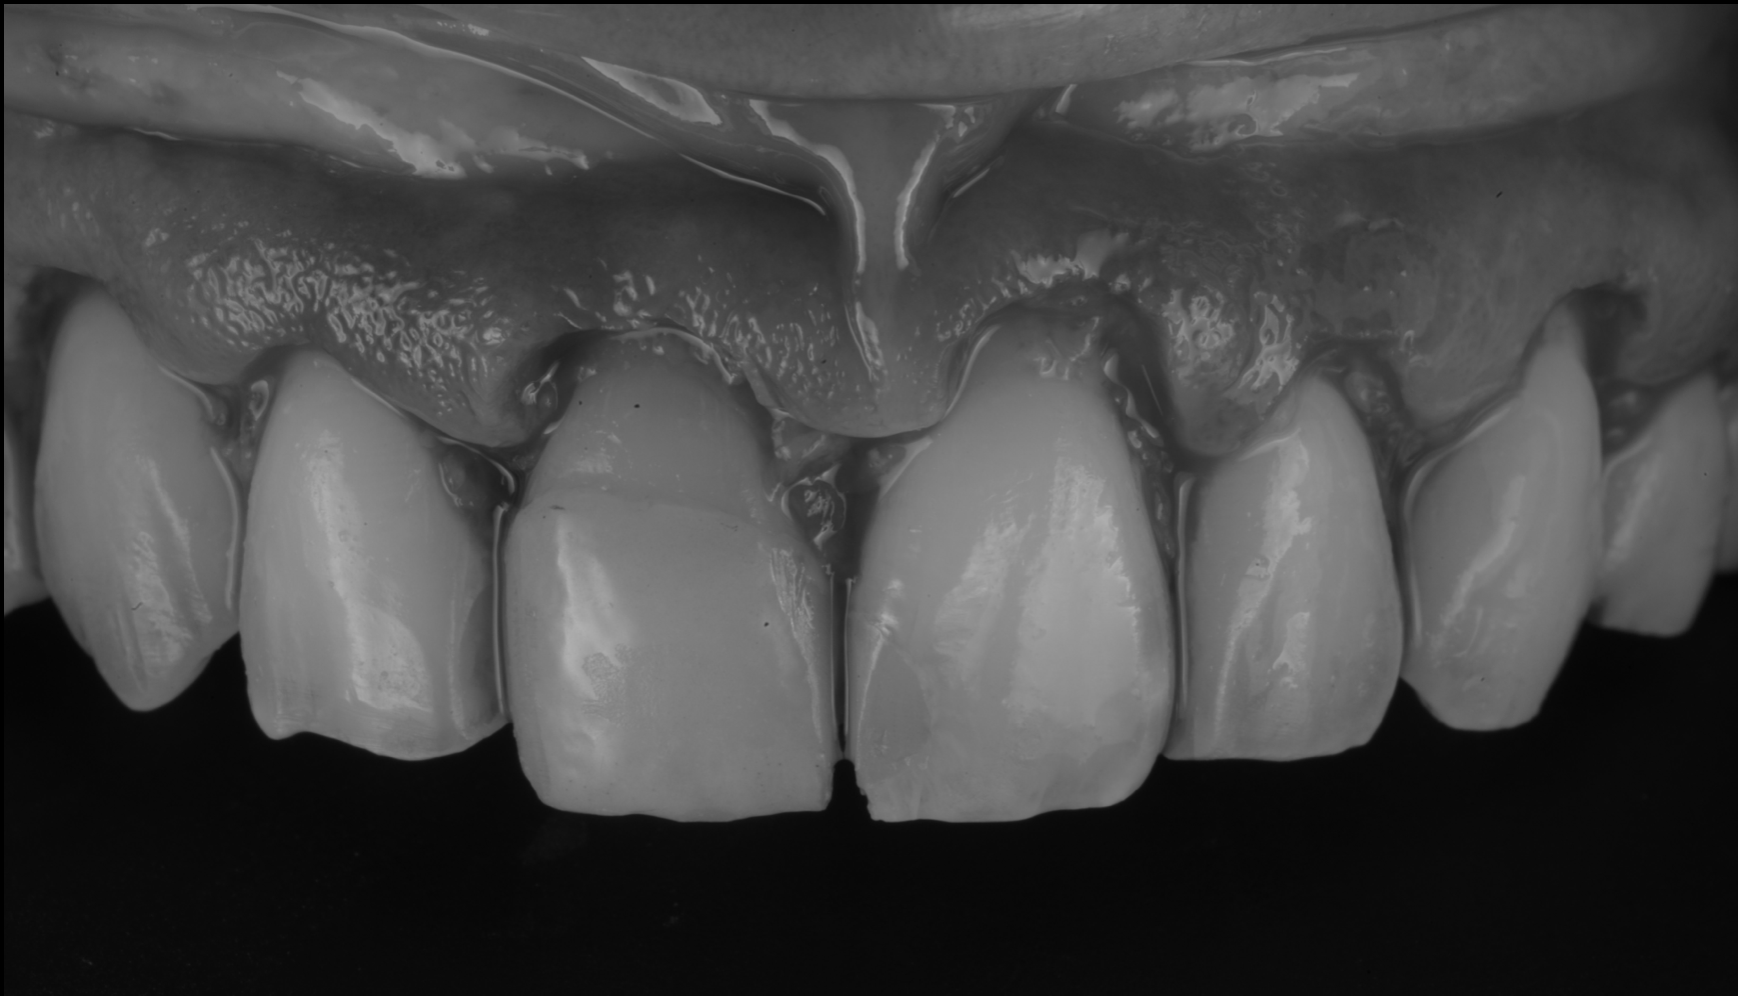

矯正終了後

術中(クラウンレングスニング)